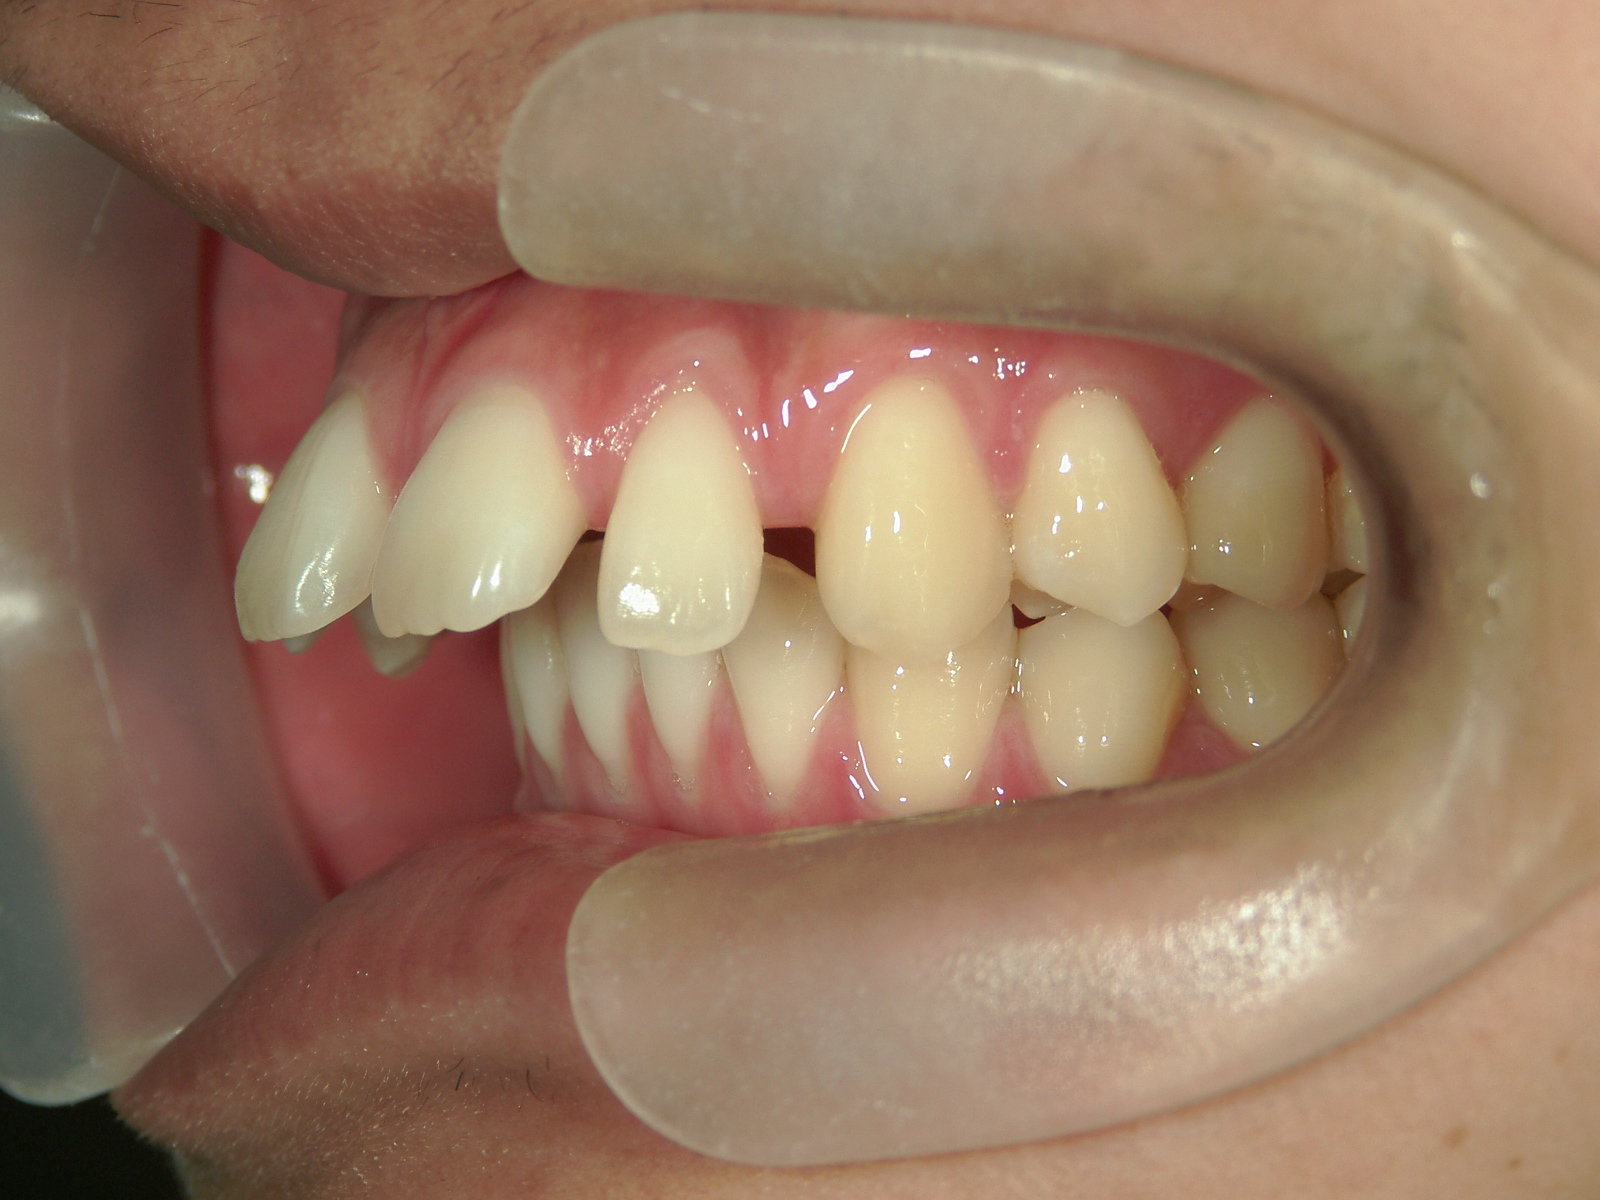

インビザライン矯正 症例(24)

主訴: 前歯の隙間が気になる。

左右上 第一小臼歯(2本)を抜歯。

カテゴリー : 隙間がある(空隙歯列)